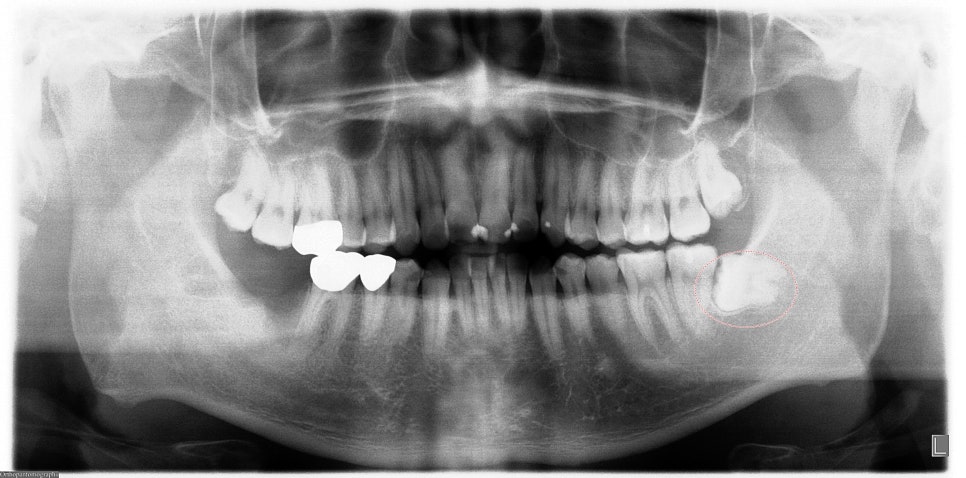

- 매복된 사랑니의 경우 시간이 지남에 따라 사랑니 주위에 물주머니가 생기는 경우가 있습니다.

이럴 경우 이 물주머니가 주변 조직을 압박하여 통증을 유발하거나 감염을 일으킬 수 있어서

신논현역 치과 스마일 뷰에서 사랑니 발치를 권유해 드립니다.